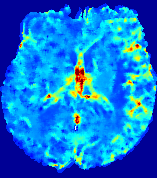

Slice #1Slice #2Slice #3Slice #4Slice #5Slice #6Dgtsuperscript𝐷gtD^{\text{gt}}Refer to captionRefer to captionRefer to captionRefer to captionRefer to captionRefer to caption(a)Refer to captionRefer to captionRefer to captionRefer to captionRefer to captionRefer to caption(b)Refer to captionRefer to captionRefer to captionRefer to captionRefer to captionRefer to caption(c)Refer to captionRefer to captionRefer to captionRefer to captionRefer to captionRefer to caption(d)Refer to captionRefer to captionRefer to captionRefer to captionRefer to captionRefer to caption(e)Refer to captionRefer to captionRefer to captionRefer to captionRefer to captionRefer to caption(f)Refer to captionRefer to captionRefer to captionRefer to captionRefer to captionRefer to captionRefer to caption000.060.060.060.120.120.120.180.180.180.240.240.240.300.300.30(mm2/s)𝑚superscript𝑚2𝑠(mm^{2}/s)

Figure 13: PIANO effectiveness and robustness testing: diffusion imaging via diffusion. Top row shows Dgtsuperscript𝐷gtD^{\text{gt}} used for simulating the ground truth pure diffusion. (a)-(f) refer to the results for D𝐷D estimated from the ground truth pure diffusion image time-series where Rician noise at levels 0%, 2%, 4%, 6%, 8%, 10% was added respectively.

Similarly, starting from the same initial condition C0superscript𝐶0C^{0} as in the ‘Advection Imaging’ experiment for each patient, we simulate concentration time-series {Cti(Ω)|i=0, 1,, 40}conditional-setsuperscript𝐶subscript𝑡𝑖Ω𝑖0140\{C^{t_{i}}\in\mathbb{R}(\Omega)|i=0,\,1,\,\ldots,\,40\} via a diffusion PDE, where we define the ground truth diffusivity D:=Dgtassign𝐷superscript𝐷gtD:=D^{\text{gt}} via the ADC map of the ISLES 2017 training set (ADC values are scaled by 0.000010.000010.00001 to ensure numerical stability):

Note this is likely not a spatially representative ground-truth for perfusion imaging, as it measures different effects from diffusion imaging. However, we still use it as a quasi-realistic pattern of diffusivity in the brain. We also added 2%, 4%, 6%, 8%, 10% levels of Rician noise to obtain simulations of ‘Diffusion Imaging’. The estimated Destsuperscript𝐷estD^{\text{est}} given concentrations of all noise levels for one patient are shown in Fig. 13, PIANO estimation results for all patients are summarized in Fig. 11 (b). Again, PIANO demonstrates its capability to recover the underlying diffusion field. In Fig. 13, when the noise level is increasing, some noisy patterns indeed appear in the associated Destsuperscript𝐷estD^{\text{est}}. Note that the ground truth diffusivity applied in this simulation experiment is about ten times larger than the diffusivity estimated in reality (Fig. 3, Fig. 4).